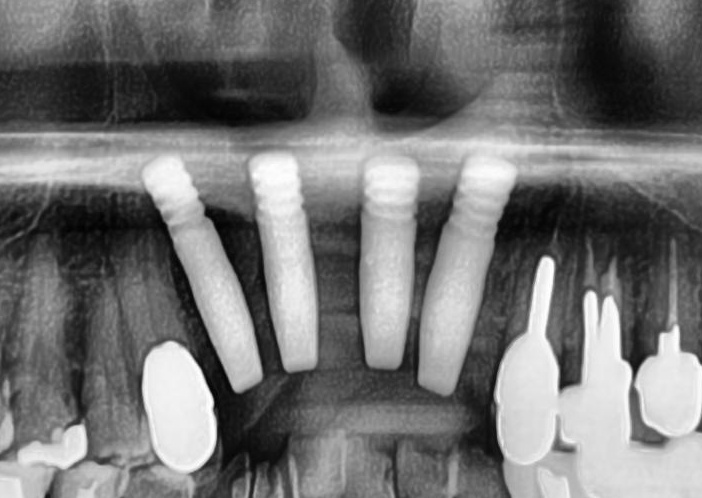

しっかりとインプラント埋め込まれた後は、動揺がないか、噛んだ時に当たらないかなどを確認して、最後にパノラマ写真を撮影して今回のオペは終了となりました。

その後は定期的にお掃除や検診に通院していただき、約3か月経過した後に、きれいな差し歯を入れていきます。